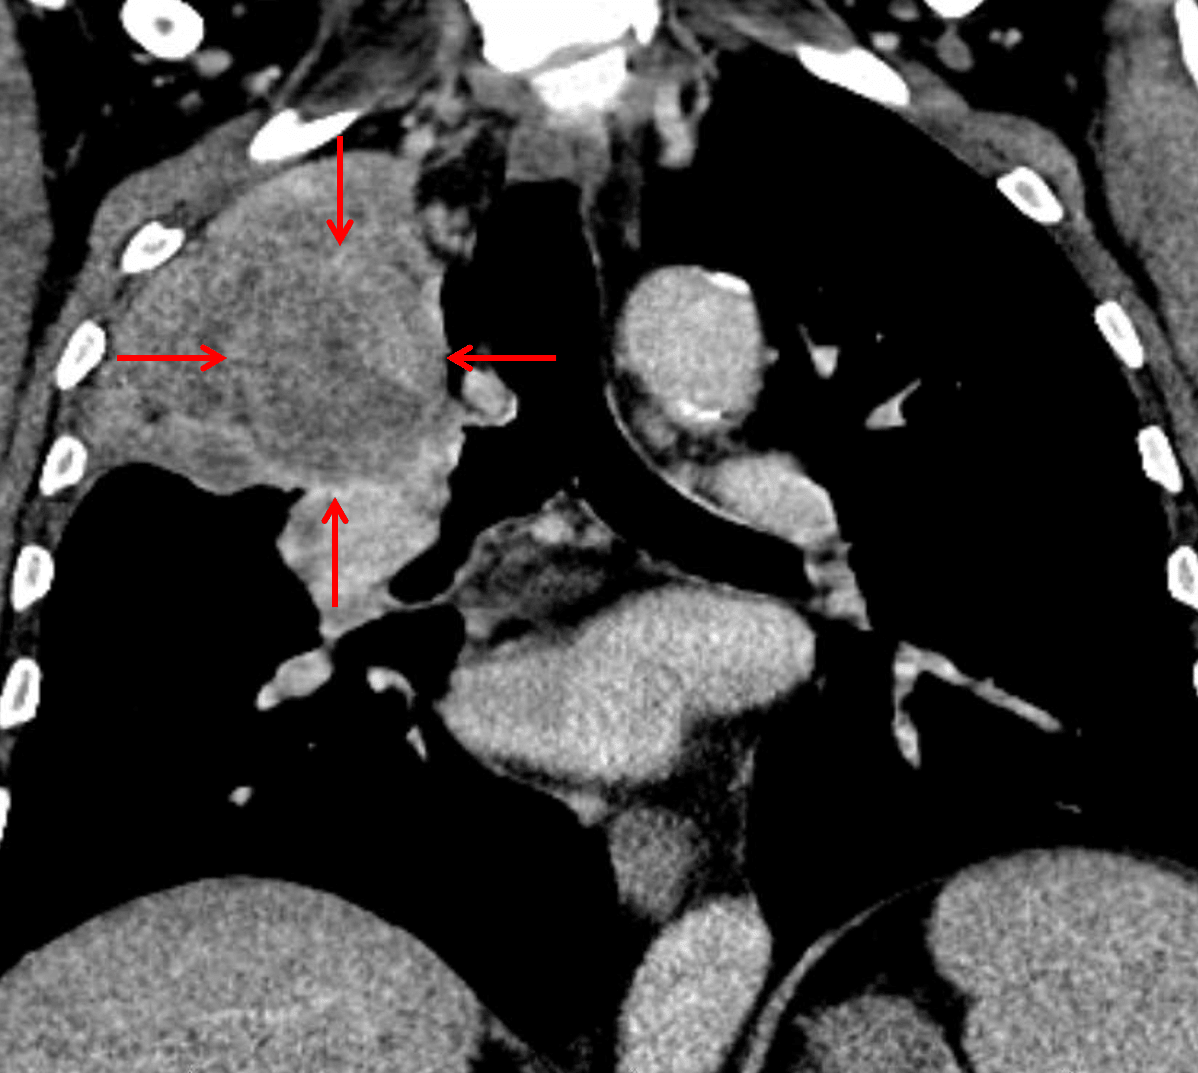

Subsequent CT confirmed the presence of a suprahilar mass with bronchial invasion (red arrows), though the mass is difficult to distinguish from the adjacent atelectatic lung.